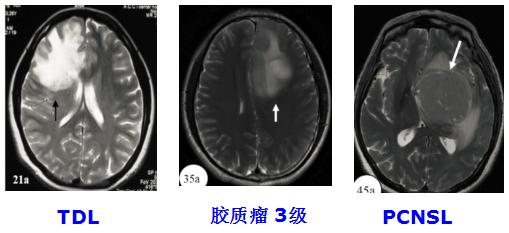

5. TDL与胶质瘤、PCNSL的影像对比

图 占位效应

(1)TDLs的MRI-T2WI往往边界清楚,胶质瘤的MRI-T2WI边界相对模糊。

(1)对胶质瘤相对特异:桥脑基底动脉包绕征、中线结构移位、胼胝体增厚及病灶的出血、坏死、囊变。

(3)TDL较特异:同心圆样病灶、增强MRI的动态演变、开环样强化、垂直于侧脑室的“梳齿征”及云片状T2病灶,边界较清楚,伴短T2边缘。